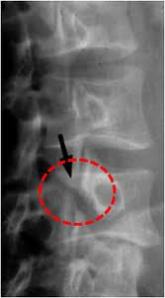

Fractura cuello femur (flecha)

[caption id="attachment_399" align="alignnone" width="300"]